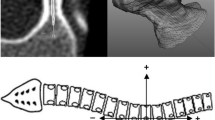

Each CT scan was opened using AMIRA with synchronized axial, coronal, and sagittal displays. The image contrast levels were standardized to enable clear soft tissue and bone demarcation at the vertebral pedicles. The relevant vertebral body was identified by counting upward from the sacrum and confirmed by counting the rib levels superiorly and inferiorly. For the pedicle to be measured, the local axial viewing plane (Fig. 1) was adjusted to be parallel to the superior and inferior endplates of the vertebrae in question (Red line in Fig. 1C) and aligned with the pedicle axis (Red line in Fig. 1B). When the superior and inferior endplate planes were not parallel owing to vertebral wedging, an orientation approximately halfway between (ie, bisecting) the two endplate inclinations was selected. The local sagittal viewing plane (Fig. 1B) then was adjusted such that it was in line with the pedicle axis and perpendicular to the local axial plane (Green line in Fig. 1A). The right pedicle was identified in a similar manner and the local viewing plane orientation again adjusted to be in line with the right pedicle axis in the axial and sagittal viewing planes.

The local (A) axial viewing plane with a sagittal slice (green line) in line with the pedicle axis, (B) sagittal viewing plane with an axial slice (red line) in line with the pedicle axis, and (C) coronal viewing plane with an axial slice (red line) approximately parallel to the superior and inferior endplates are shown.

Anatomic landmarks were identified and measured on each pedicle (Fig. 2). The 3-D coordinates of 17 points (points A through Q) were identified on each pedicle (34 in total for each vertebra), with the appropriate distances and angles between these points (pedicle width, inner cortical pedicle width, pedicle length, chord length, transverse pedicle angle, pedicle height, inner cortical pedicle height, sagittal pedicle angle) calculated from the landmark locations (Fig. 2). These measurement definitions are similar to those described in the literature [7, 16, 18, 31], however we have taken measurements with the coronal, sagittal, and axial planes oriented to better represent the anatomic axes of the pedicle.

(A) This CT scan of a thoracic vertebrae in the local axial plane shows the outer cortical pedicle width (AC) and the inner cortical pedicle width (BD), where A is the lateral outer cortex margin, B is the lateral inner cortex margin, C is the medial outer cortex margin, and D is the medial inner cortex margin. (B) This scan of a thoracic vertebrae in the local axial plane shows chord length (EF), pedicle length (FG), and transverse pedicle angle (angle between EG and HI), where E is the anterior edge of the vertebral body along the pedicle axis, F is the posterior edge of the vertebra along the pedicle axis, G is a point in line with the posterior longitudinal ligament along the pedicle axis, H is the sagittal midvertebral line at the anterior aspect of the vertebral body, and I is the sagittal midvertebral line at the meeting of the laminae. (C) This CT scan of a thoracic vertebrae in the local sagittal plane shows the pedicle height (JL) and inner cortical pedicle height (KM), where J is the superior outer cortex margin, K is the superior inner cortex margin, L is the inferior outer cortex margin, and M is the inferior inner cortex margin. (D) This scan of a thoracic vertebrae in the local sagittal plane shows the sagittal pedicle angle (angle between the line NO and PQ), where NO is a line between the anterior (N) and posterior (O) aspects of the vertebrae angled midway between the superior and inferior endplates angles, while PQ is a line between the anterior (P) and posterior (Q) edges of the vertebrae along the pedicle axis in the sagittal viewing plane.